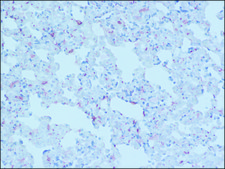

Application:

technique(s)

immunoblotting: 0.25-0.5 g/mL, immunofluorescence: 2.5-5 μg/mL, immunohistochemistry: 10-20 μg/mL